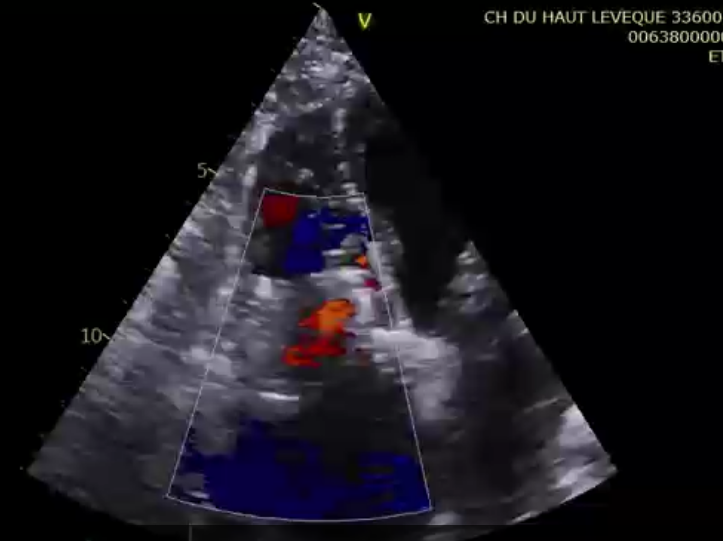

術前超聲提示大量三尖瓣反流

術后超聲提示微量瓣周漏